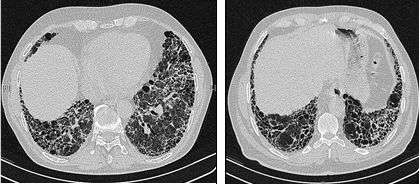

The radiological evaluation through HRCT is an essential point in the diagnostic pathway in IPF. HRCT is performed using a conventional computed axial tomographic scanner without injection of contrast agents. Evaluation slices are very thin, 1–2 mm.

Typical HRCT of the chest of IPF demonstrates fibrotic changes in both lungs, with a predilection for the bases and the periphery. According to the joint ATS/ERS/JRS/ALAT 2011 guidelines, HRCT is an essential component of the diagnostic pathway in IPF which can identify UIP by the presence of:[2]

- Reticular opacities, often associated with traction bronchiectasis

- Honeycombing manifested as cluster cystic airspaces, typically of comparable diameters (3–10 mm) but occasionally large. Usually sub-pleural and characterized by well-defined walls and disposed in at least two lines. Generally one line of cysts is not sufficient to define honeycombing

- Ground-glass opacities are common but less extensive than the reticulation

- Distribution characteristically basal and peripheral though often patchy.